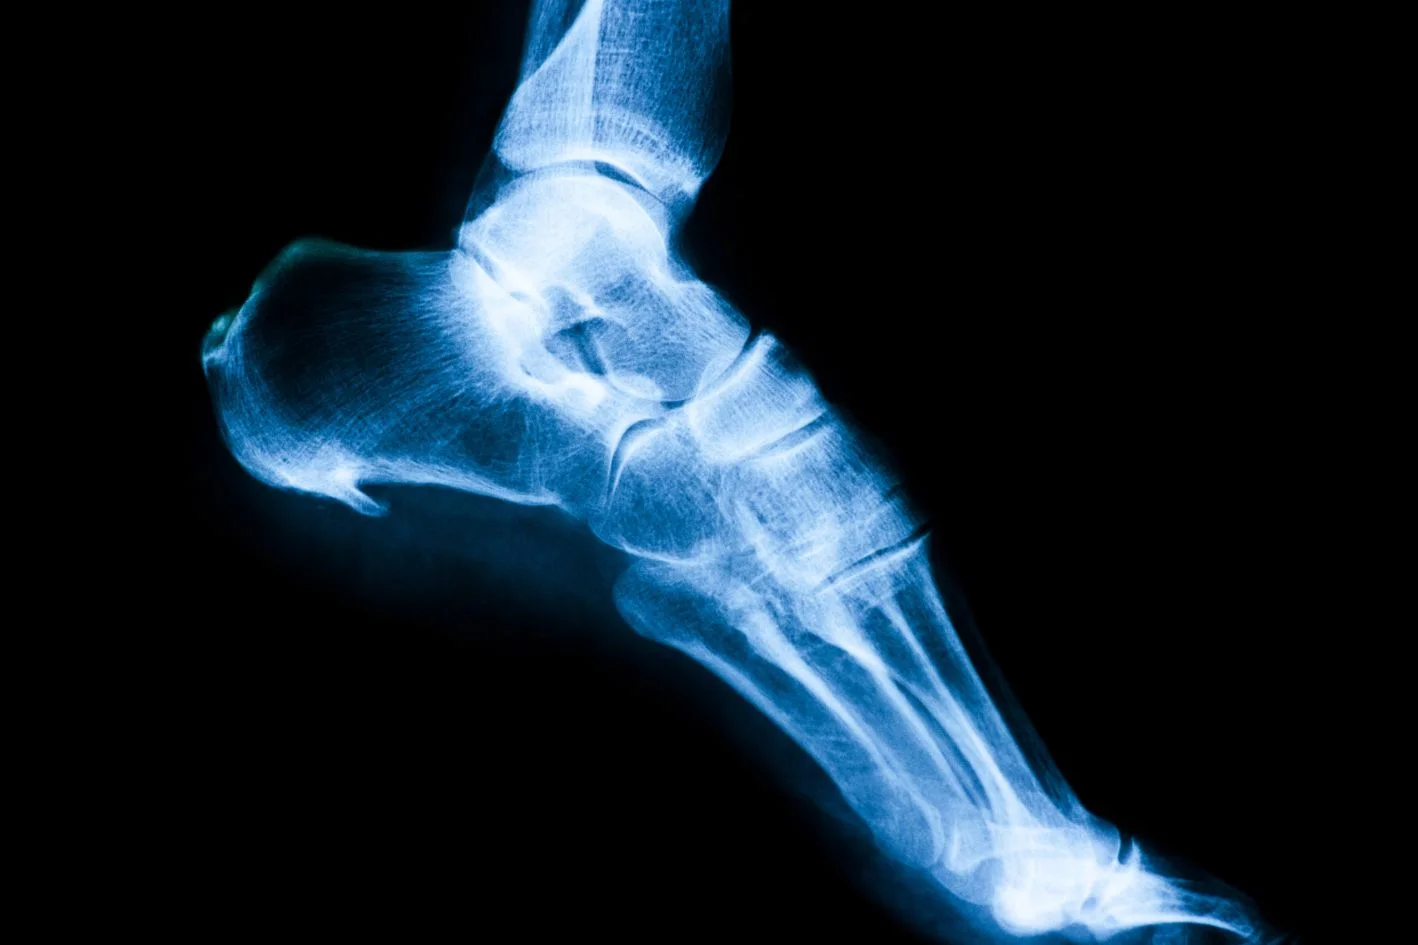

x-ray image showing a heel spur under the foot

If you’ve had an X-ray for heel pain, there’s a good chance you’ve been told you have a “heel spur”.

A heel spur is a small bony projection that can form at the base or the back of the heel bone.

It develops gradually over time due to repetitive stress and traction on the heel bone, where the plantar fascia and Achilles tendon attach.